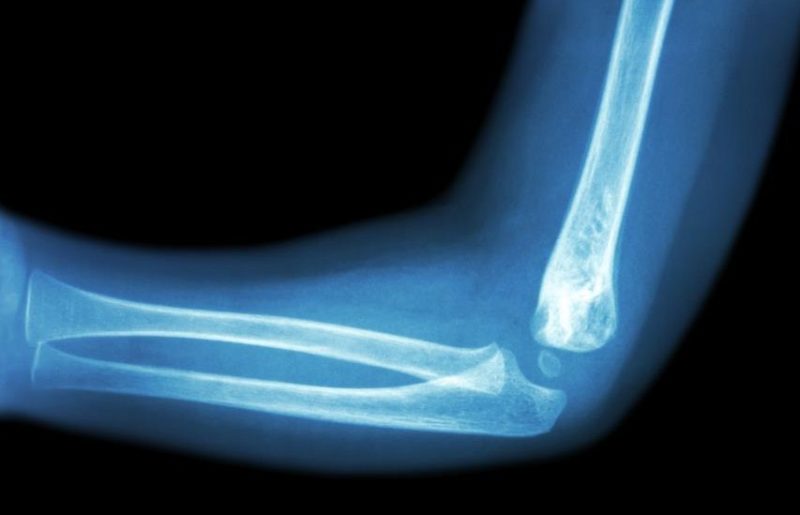

The first symptom of osteoarthritis is elbow pain. And if the movement of the elbow is restricted in addition to the pain, the suspect of osteoarthritis deformity becomes dark. To be restricted is to say “I can not straighten” or “I can not bend”.The elbow joint is a set of three joints. In the elbow part, the joints connect three bones of the humerus of the lower arm and the radius on the thumb side of the forearm and the ulna at the side of the little finger.

These three bones each combine two to form three joints, which are grouped together at the elbow joint. It is pretty complicated.

Because of this complex joint, there are many cartilage surfaces that make up the joint. There are various things that cause damage to this cartilage surface.